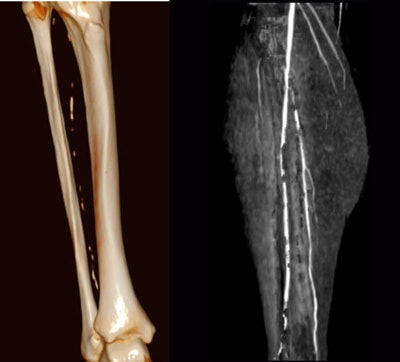

When the vessels in the lower leg are heavily calcified it's hard to tell what's going on with dynamic MRA. But acquire the images with dynamic CT, then subtract the bone, and the calcium and status of the blood flow is revealed, he said.

When the noncontrast series of images are subtracted from the bone-subtracted contrast-enhanced dynamic series, "you can finally see there is still sufficient runoff in the area of the heavy calcified plaque that is also subtracted when you subtract the complete noncontrast scan from the dynamic series," he said. And happily, the patient gets to skip the intervention.